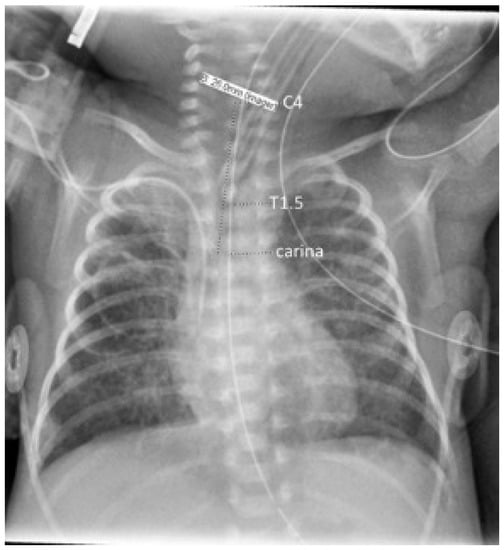

Vertebral bodies were identified by counting ribs from the first to the 12th (if present), thus designating T12, before counting the cephalad to locate the carina, T1, and C4. Carina position was used in reference to the vertebral level on an interval scale, with interspaces designated as half levels. Tracheal length was measured from carina to mid C4, the neonatal cricoid level [30,31], as shown in Figure 1. The cursor built into the imaging software (IntelliSpace PACS Enterprise 4.4, Philips Medical Systems, Amsterdam, The Netherlands) was then used to measure the distances from carina to mid C4 length (tracheal length), carina to mid-T1, and carina to T1.5 (T1–T2 interspace), to the nearest mm. T1 has been shown by Thayyil et al. to be a superior radiological reference marker for the neonatal mid-trachea [32]. T1.5 has been used in our clinical quality improvement work as the operationally defined target for the ETT tip; however, acceptable positions of the tube tip (requiring no adjustment) range between the top of T1 and the bottom of T2. The software’s contrast limited adaptive histogram equalization (CLAHE) tool was applied to images to optimize contrast for the visualization of the carina.

Figure 1.

Chest radiograph illustrating annotations of anatomical landmarks with the dashed line markers, underlying the measurements; tracheal length was taken as the carina–C4 distance.